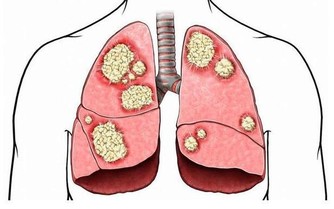

肺癌是“癌症之王”,是人類死亡的頭號殺手。肺癌的發病率男性多於女性,城市多於農村。

肺癌不是吸煙一族的專利,這些致病因素更可怕

肺癌並非吸煙一族的專利,經常接觸二手煙、做飯的女性也是肺癌的高危人群。肺癌的致病因素比較複雜,空氣污染、環境因素、粉塵、刺激性氣味環境、遺傳史等等都是導致肺癌的致命因素,它就像一種慢性病一樣,在某種致病因素的長期刺激下,正常細胞會發生癌變,慢慢地形成腫瘤。據了解,閆懷禮在河北涿州拍攝一部叫《俏羅城》的電視劇。當地的蒼蠅、蚊子特別多,當時有一場戲拍戲的現場噴灑了很多敵敵畏,很多人都因為濃重的味道離開了,當時閆懷禮嗅覺不好感覺不到,長時間處在敵敵畏濃重的環境裡面,拍戲空擋還在那裡休息,好友六小齡童分析這是他患病的誘因之一,再加上多年拍戲工作太過勞累,閆懷禮才患上了肺癌。

肺癌幫介紹,肺癌是一種高隱藏性癌症,潛伏期最長達10年。早期沒有明顯症狀,當有的人發現腰痛、腿疼、肩痛的時候,可能肺癌已經發生了轉移,但前期沒有任何症狀。這樣的例子生活中很常見,也給我們的健康敲響了警鐘,每年定期體檢和癌症篩查是很有必要的。